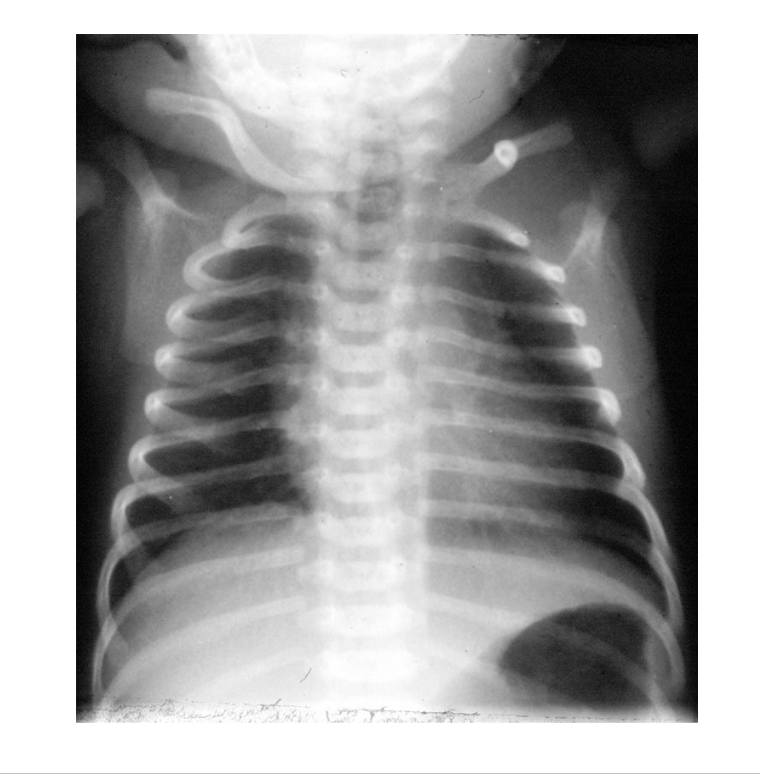

what kind of plain film is attached?

a neonatal AP plain film